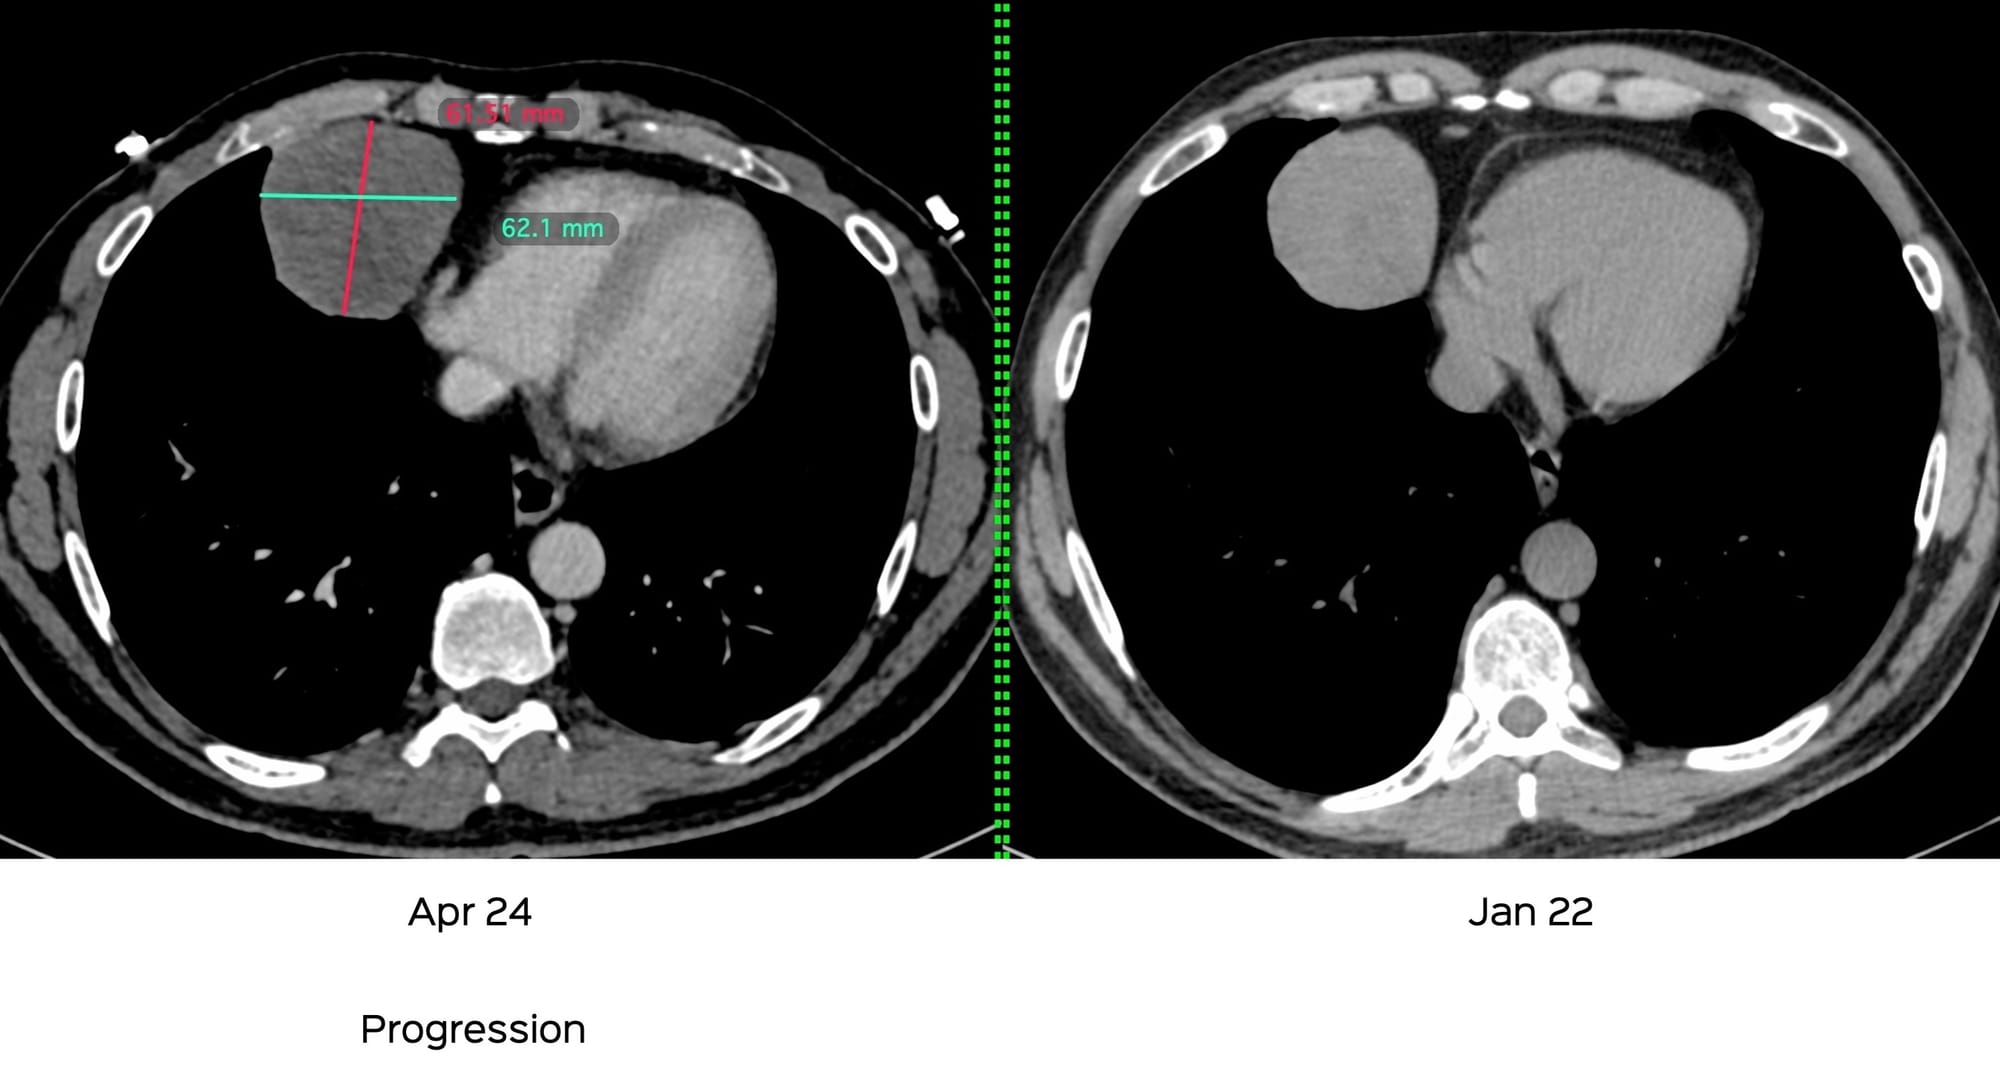

This 53-yrs old man came with an incidental, solid, enhancing medial cardiophrenic angle mass that kept growing over 8 years.

A biopsy was attempted but abandoned due to bleeding. Mortally scared, he did not agree to a biopsy till recently when it had grown even further.

A biopsy was done and the diagnosis was SFTP.

SFTPs can be diagnosed reliably on CT scan as solid enhancing, often incidental asymptomatic, pleural masses that grow slowly with minimal uptake on PET/CT, in the 50-70 years age group.